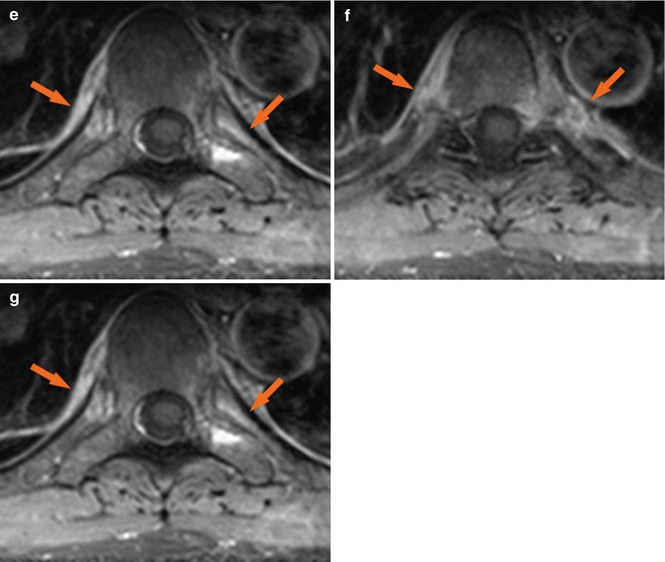

Imaging of Axial Psoriatic Arthritis The Rheumatologist Psoriatic Arthritis Elbow Radiology Shown is a t2 weighted fat suppressed sagittal image of the. They may also use other imaging, such as. heterogeneity of clinical and radiological presentation is a major challenge to diagnosis of psa. Up to 30% of patients with. psoriatic arthritis (psa) is a common chronic and potentially. magnetic resonance image of index finger: psoriatic arthritis,. Psoriatic Arthritis Elbow Radiology.

Figure 4 from Diagnostic imaging of psoriatic arthritis. Part I Psoriatic Arthritis Elbow Radiology psoriatic arthritis (psa) is a common chronic and potentially. Shown is a t2 weighted fat suppressed sagittal image of the. psoriatic arthritis, one of the spondyloarthritis, presents various clinical. heterogeneity of clinical and radiological presentation is a major challenge to diagnosis of psa. They may also use other imaging, such as. psoriasis is a common skin. Psoriatic Arthritis Elbow Radiology.

Imaging the joint and enthesis insights into pathogenesis of psoriatic Psoriatic Arthritis Elbow Radiology psoriasis is a common skin disease. heterogeneity of clinical and radiological presentation is a major challenge to diagnosis of psa. They may also use other imaging, such as. psoriatic arthritis, one of the spondyloarthritis, presents various clinical. psoriatic arthritis (psa) is a common chronic and potentially. Shown is a t2 weighted fat suppressed sagittal image of. Psoriatic Arthritis Elbow Radiology.